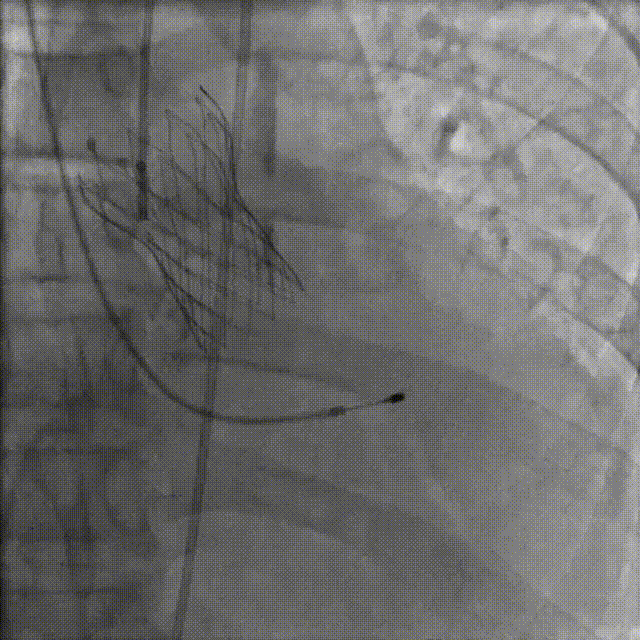

主动脉根部造影

20mm球囊预扩后瓣膜开始定位

工作位造影:左右窦侧瓣架偏深

回收后重新调整释放

工作位造影:位置理想

瓣膜逐个缓慢脱钩

23mm球囊后扩改善形态

最终造影:位置理想,形态良好,无漏